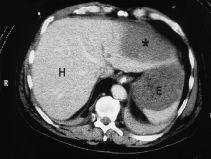

Fig. 1. TAC abdominal con administración de contraste intravenoso en donde se muestra el hematoma subcapsular hepático (*). H: hígado, y E: estómago.

Se trataba de un paciente alemán de 62 años con antecedentes de IAM anteroseptal, disfunción ventricular severa, portador de un stent coronario y en tratamiento actual con anticoagulantes orales (INR 1,5), ácido acetilsalicílico, inhibidores de la ECA y nitratos. Previamente bien, presentó un paro cardiorrespiratorio en la vía pública por lo que se iniciaron maniobras de RCP básica. A la llegada de la ambulancia medicalizada se diagnosticó una fibrilación ventricular que revirtió a ritmo sinusal tras 2 choques eléctricos. Ingresó en la unidad de cuidados intensivos sedado y conectado a ventilación mecánica. La gasometría arterial con FiO2 1 indicó: pH, 7,18; PaCO2, 61 mmHg; PaO2, 131 mmHg, y HCO3, 22 mmol/l. Su tensión arterial era de 95/60 mmHg, el pulso de 85 lpm y el ECG ritmo sinusal con rectificación del segmento ST en cara inferior. El resto de la exploración no reveló hallazgos significativos. Se suspendió la sedación y a las 2 horas del ingreso se objetivó un paciente con apertura espontánea de ojos y capaz de localizar dolor, taquipneico y desadaptado de la ventilación mecánica, hemodinámicamente estable pero con tendencia a la oliguria, destacando un abdomen distendido, doloroso y defendido a la palpación. Una nueva gasometría arterial mostró acidosis metabólica (pH, 7,22; PaCO2, 17 mmHg; PaO2, 228 mmHg, y HCO3, 7 mmol/l) refractaria a la administración de bicarbonato y se obtuvo una hemoglobina de 13,6 g/dl. Mediante ecografía abdominal se demostró una dilatación de asas de intestino delgado y líquido libre intraperitoneal. Una radiografía de abdomen descartó neumoperitoneo. Se practicó laparotomía exploradora, siendo los hallazgos hemoperitoneo masivo por rotura hepática con sección del ligamento redondo y del coronario que se repararon y hematoma subcapsular hepático importante. El paciente reingresó en la UCI con su trastorno metabólico corregido, manteniendo tensión arterial y diuresis adecuadas. El hematoma subcapsular hepático se controló mediante TAC abdominal (fig. 1) sin evidenciar cambios significativos. El paciente fue trasladado a su país de origen.